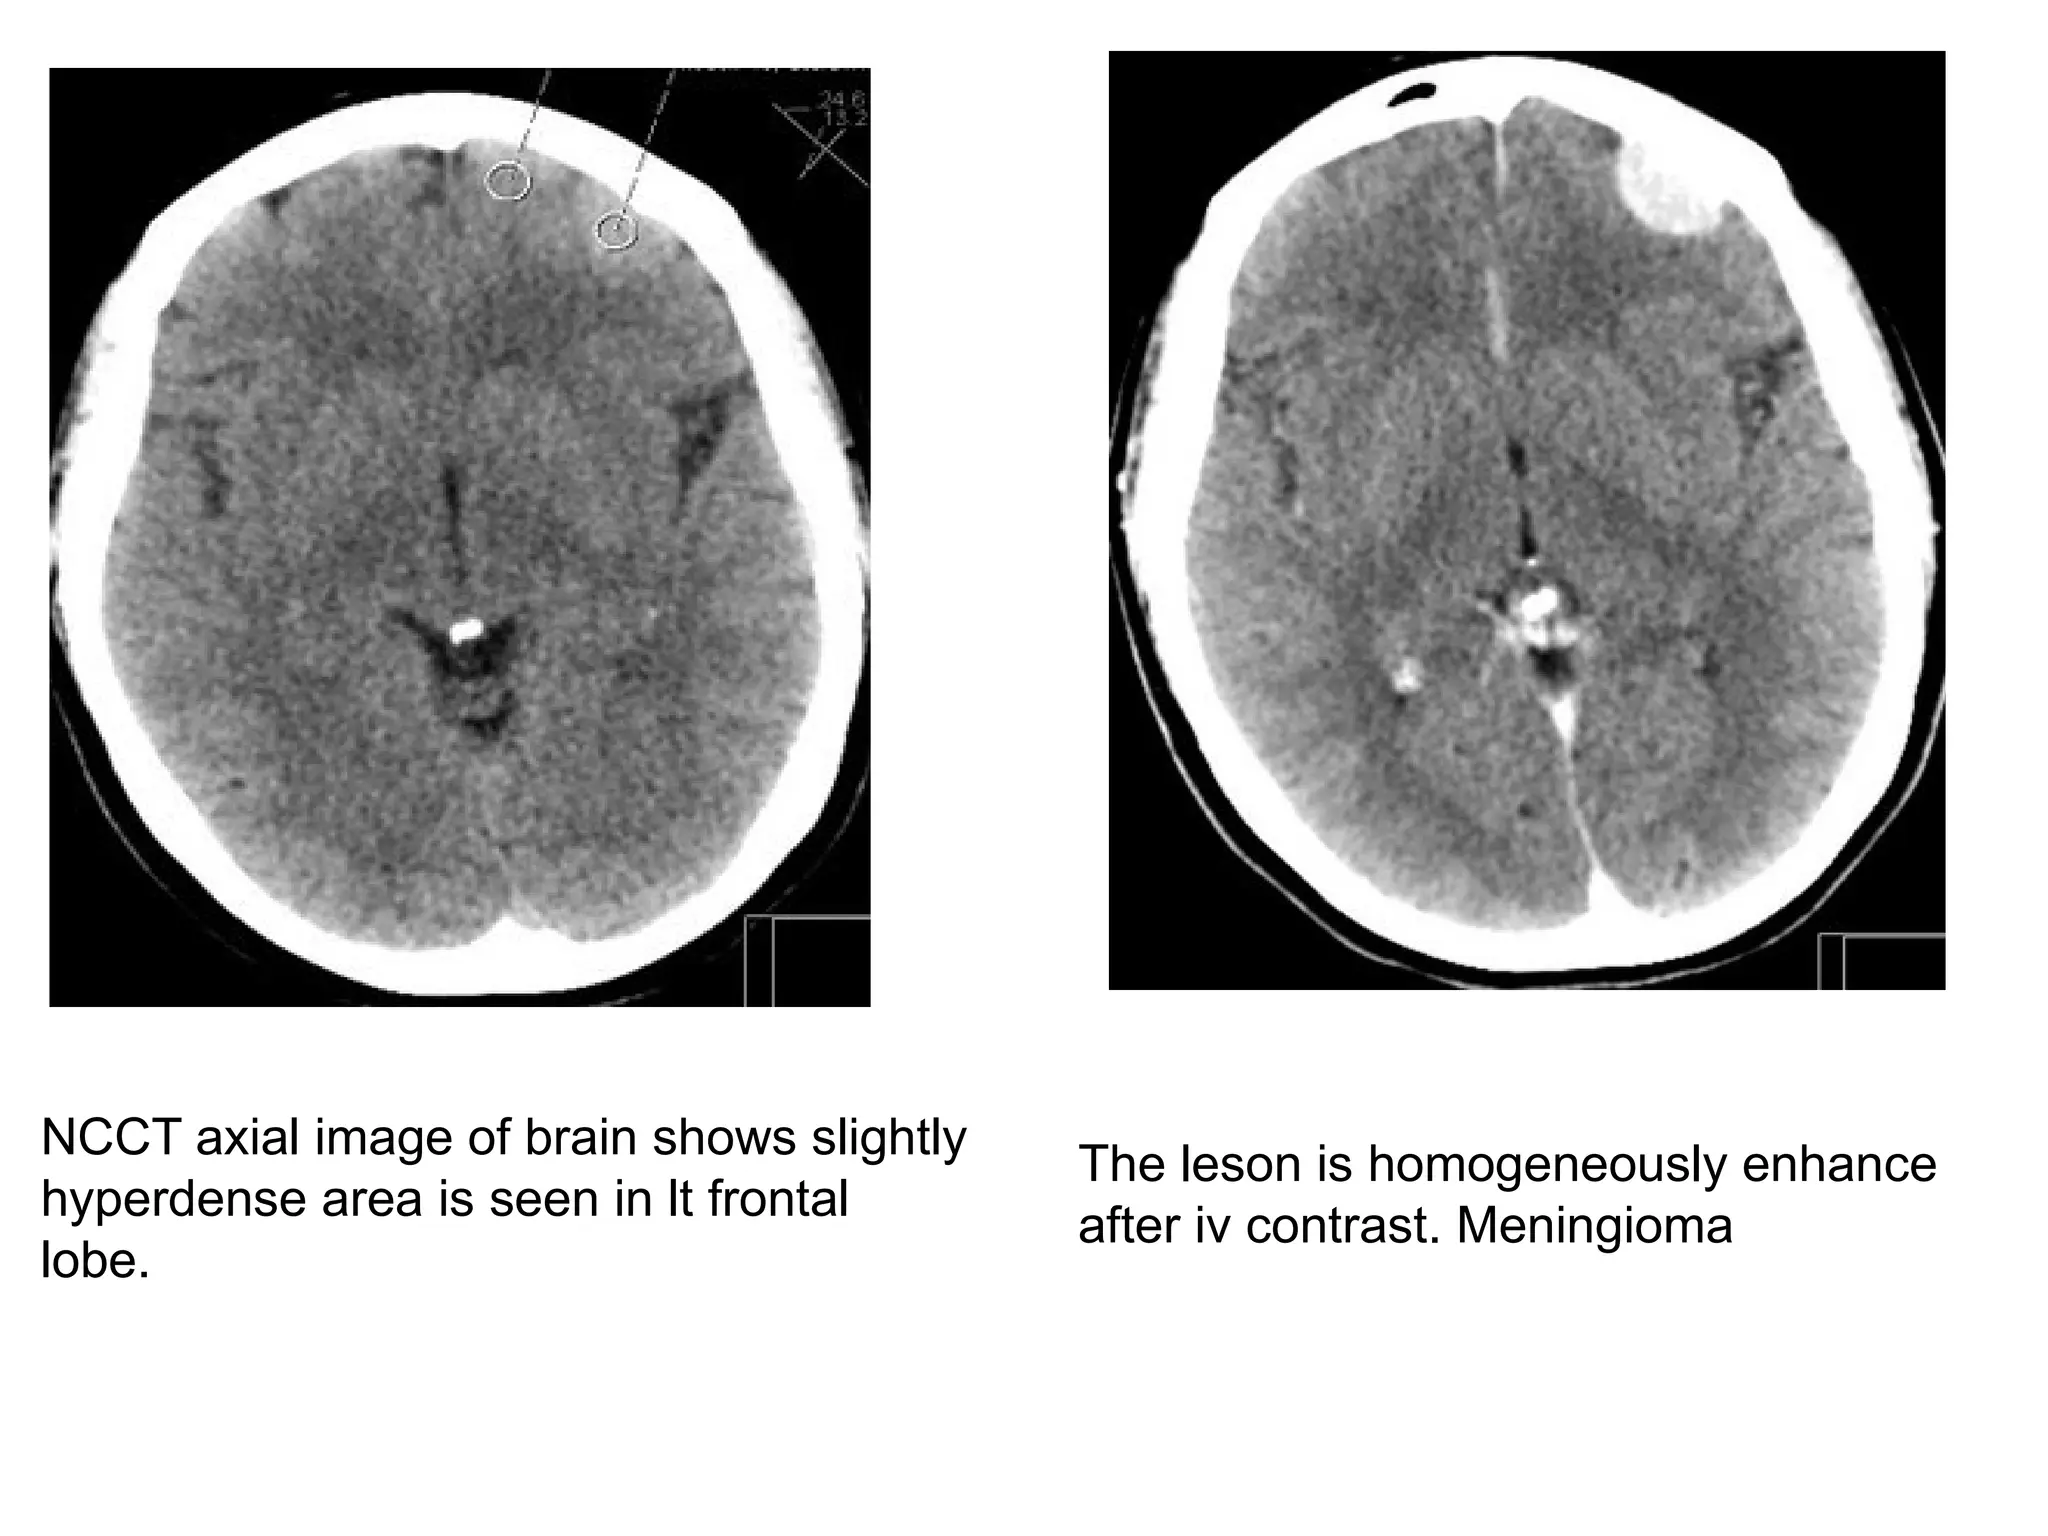

NCCT axial image of brain shows slightly

hyperdense area is seen in lt frontal

lobe.

The leson is homogeneously enhance

after iv contrast. Meningioma